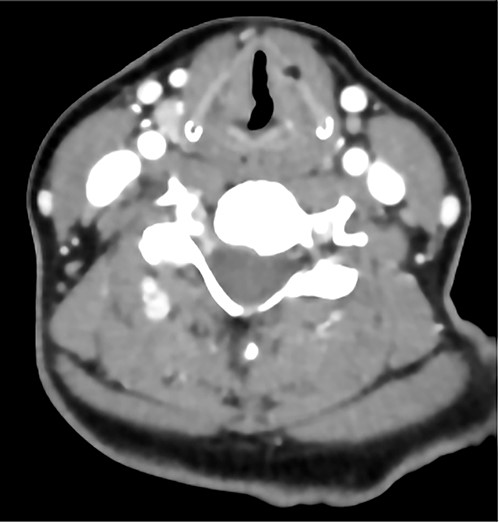

Biopsies show polypoid squamous epithelium-lined stroma containing abundant amorphous, eosinophilic acellular hyaline material (Hematoxylin and Eosin stain; a, b). This material is Alcian blue positive (c), PASD positive (d), EVG positive (e) and Trichrome (for fibrin) negative (f).

Histopathology showed abundant deposits of acellular amorphous hyaline material in the subepithelial stroma. This material was diastase-resistant Periodic acid–Schiff (PAS) positive, and stained with Alcian blue (pH 2.5) and Elastin van Gieson (EVG). It was negative for Congo Red (amyloid) and Trichrome stain (for fibrin). The overall features were consistent with LP (Fig. 4). No clinically relevant variants were identified in the ECM1 gene by sequence analysis. The patient was referred to internal medicine to rule out the systemic manifestations of the disease; their investigations were unremarkable. The patient was given the options of surgical and medical management; she preferred medical management. She was managed conservatively with an anti-reflux medication, oral corticosteroids for 14 days and postoperative voice rest instructions. She was reassessed 3 and 6 months postoperatively with stable laryngeal symptoms and resolved dysphagia and was given a yearly follow-up for reassessment.